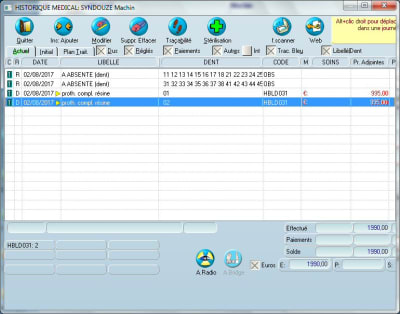

Pour rigoler. Un patient se présente avec un complet haut et bas. Dans Julie, schéma initial, on enlève toutes les dents et on met HBLD035 (2 complets résine). Cela ne s'affiche pas. Pour avoir les complets sur le schéma, il faut remettre les dents!Bug.

La hot line m'a fait remettre les dents. Cela pose un pb car je dois refaire les complets ( donc sur des dents). J'ai opté pour la solution de bien enlever toutes les dents sur le schèma initial et ne pas voir les anciens complets sur le schèma.

Ce que je trouve dommage avec Julie, JC, c'est que si on rentre par exemple en mode texte 2 rateliers complets résine, on ne les voit pas en mode graphique. Il faut obligatoirement passer par le mode graphique.

Qu'on passe par l'un ou l'autre mode (le debat n'est pas la) pour la saisie d'un acte, on devrait le visualiser en mode graphique.

Ca fonctionne, merci cyber, il faut sélectionner l'acte prédéfini par Julie "A absente" que tu as nommé par exemple ABS dans le paramétrage des actes, que tu sois en mode graphique "bouche" ou en mode texte.

Puis on code classiquement les deux app. résine 14 dts.

Et le visu "bouche" est OK

Sur ton graphique, je ne vois pas les complets. C'est ce qui me manque. Le patient vient avec 2 complets en bouche.

Schéma initial:Patient sans dents, enlevées une par une sur le schéma.

Schéma plan de TT: C'est ce que je voudrai avoir sur le schéma initial, patient avec complets.